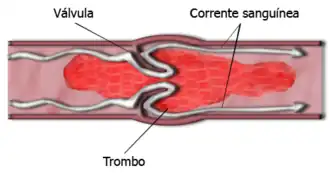

| Esquematização de isquemia por trombose. | |

Isquemia (do grego ισχαιμία; isch- restrição, hema sangue) é a falta de fornecimento sanguíneo para um tecido orgânico devido a obstrução causada por um trombo, seja ele formado por placas gordurosas ou por coágulos sanguíneos. Como o sangue, através das hemácias (glóbulos vermelhos), leva o oxigênio às células, a isquemia resulta em falta de glicose e de oxigenação nas células (hipóxia).[1] O local mal oxigenado tende a ficar roxo e se não for tratado com urgência pode causar a morte. Segundo a OMS, em 2011 foi a maior causa de mortes no mundo, com mais de 7 milhões de mortes de isquemias cardíacas e pelo menos mais 3 milhões por isquemias cerebrais ou pulmonares.[2]

O tipo de isquemia depende da área afetada e dos problemas causados. A isquemia de uma parte do coração (músculo cardíaco denominado "miocárdio") leva ao infarto, devido a obstrução do fluxo sanguíneo por um trombo gerando infarto agudo do miocárdio (conhecido popularmente como infarto do coração, ou IAM).